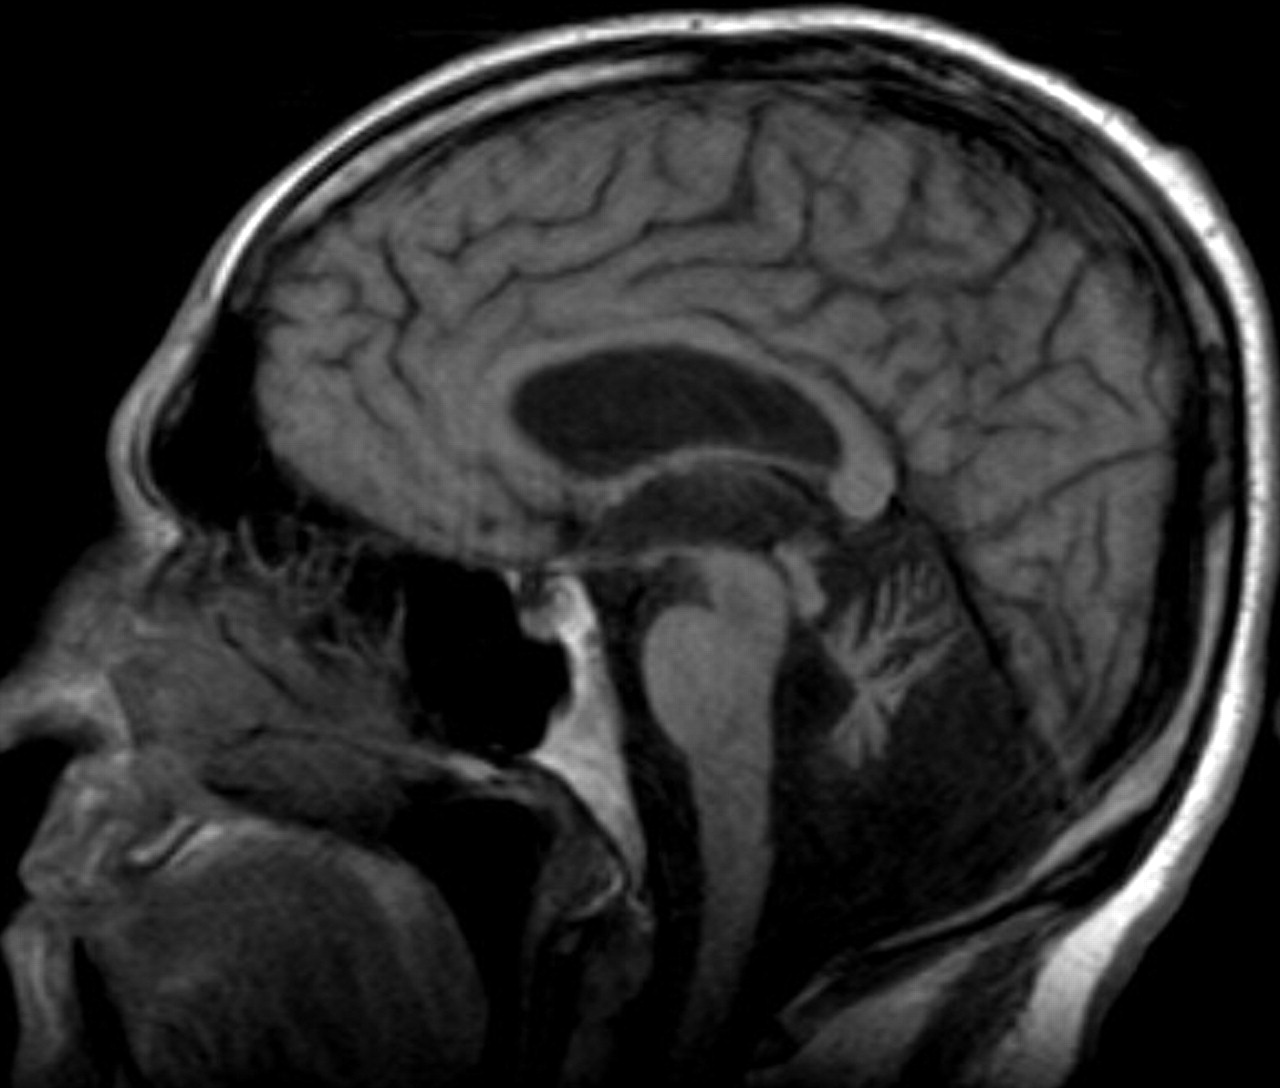

社论的作者迈克尔·j·Noetzel探讨基因组技术先进的能力描述以前未确诊的脑白质营养不良,导致表型的扩张包括不典型的患者。四个例子(表),包括Gorospe等人的报告MLC1突变导致megalencephaly与脑白质病囊肿,是著名的成人疾病的识别最初似乎是早发性疾病的孩子。磁共振成像已经被证明是非常有用的在定义脑白质营养不良,基于其敏感性展示髓鞘的畸形发展。扩散张量磁共振成像和光谱先生可提高诊断脑白质病变的能力,尤其是在成年人谁特异性的白质异常频繁。